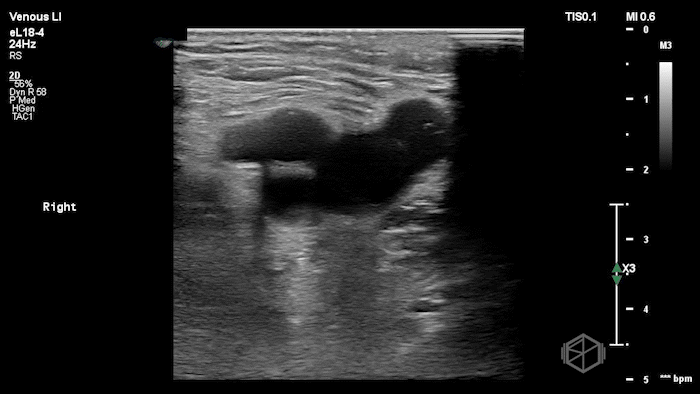

A lower extremity DVT ultrasound performed by Dr. Koutsounadis demonstrated the following:

The POCUS shows a right common femoral vein thrombus. Family members reported that the patient had previously been diagnosed with a DVT very recently and was on apixaban.

The thrombus appeared predominantly hypoechoic to nearly anechoic, making it difficult to appreciate on B-mode imaging alone. However, incomplete compressibility of the vein confirmed the presence of thrombus.

Diagnosis: Right common femoral partially occlusive DVT